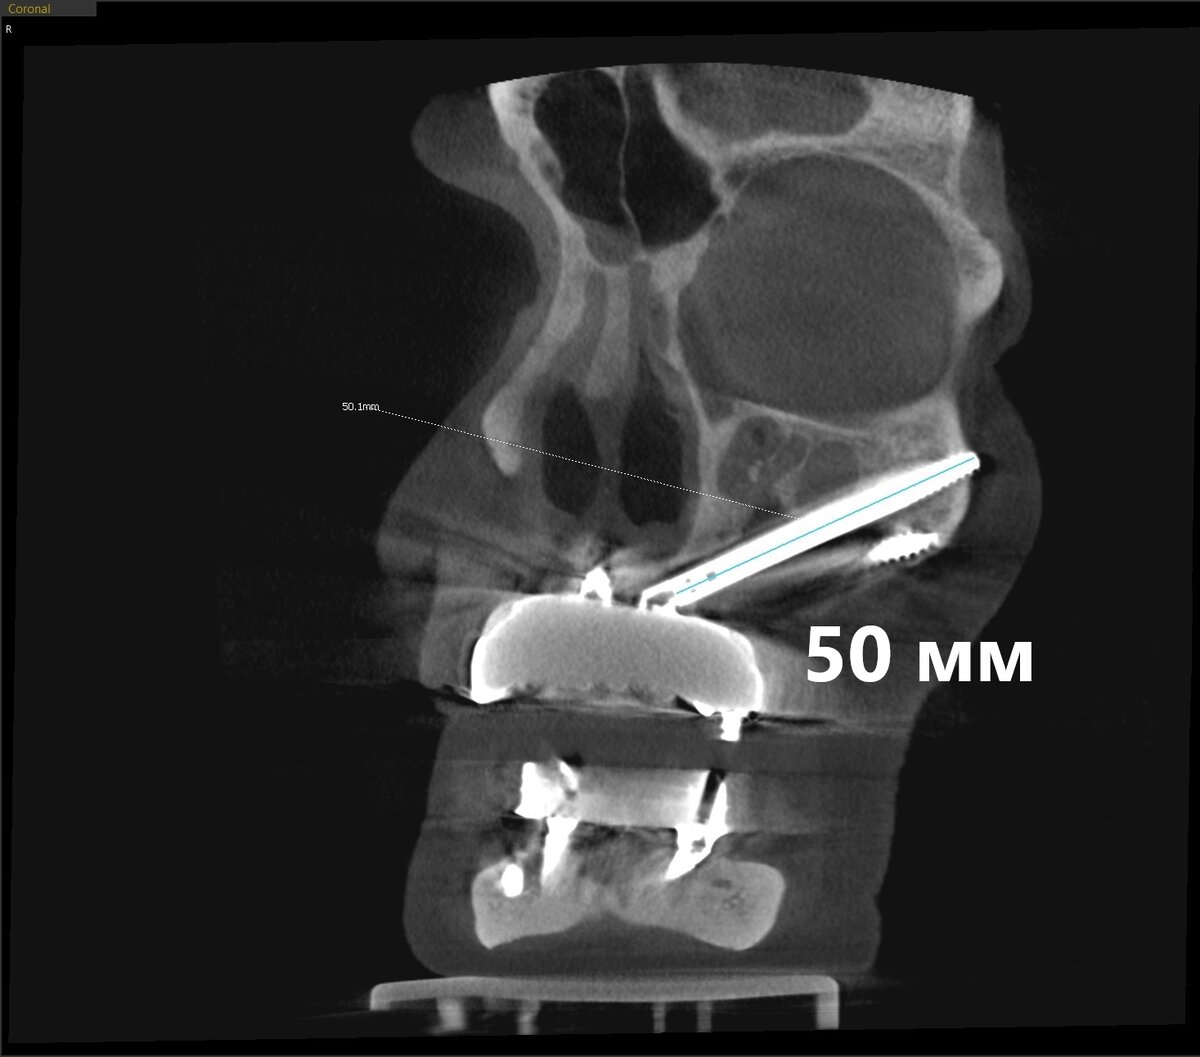

Система Nobel, сверхдлинные имплантаты Zygoma. Пациентке были установлены 4 таких имплантата - 2 покороче (около 34 мм), 2 длинных (около 50 мм). Один обычного размера - под нос.

В наших классических тоталах имплантаты 18 мм считаются длинными! Далеко не каждому при "всё на 4-х" удаётся имплантировать такую роскошь. А тут - 5 см.

Длинный "болт":

Посмотрим одну сторону (левую, справа точно то же самое) - один длинный имплантат и один покороче: